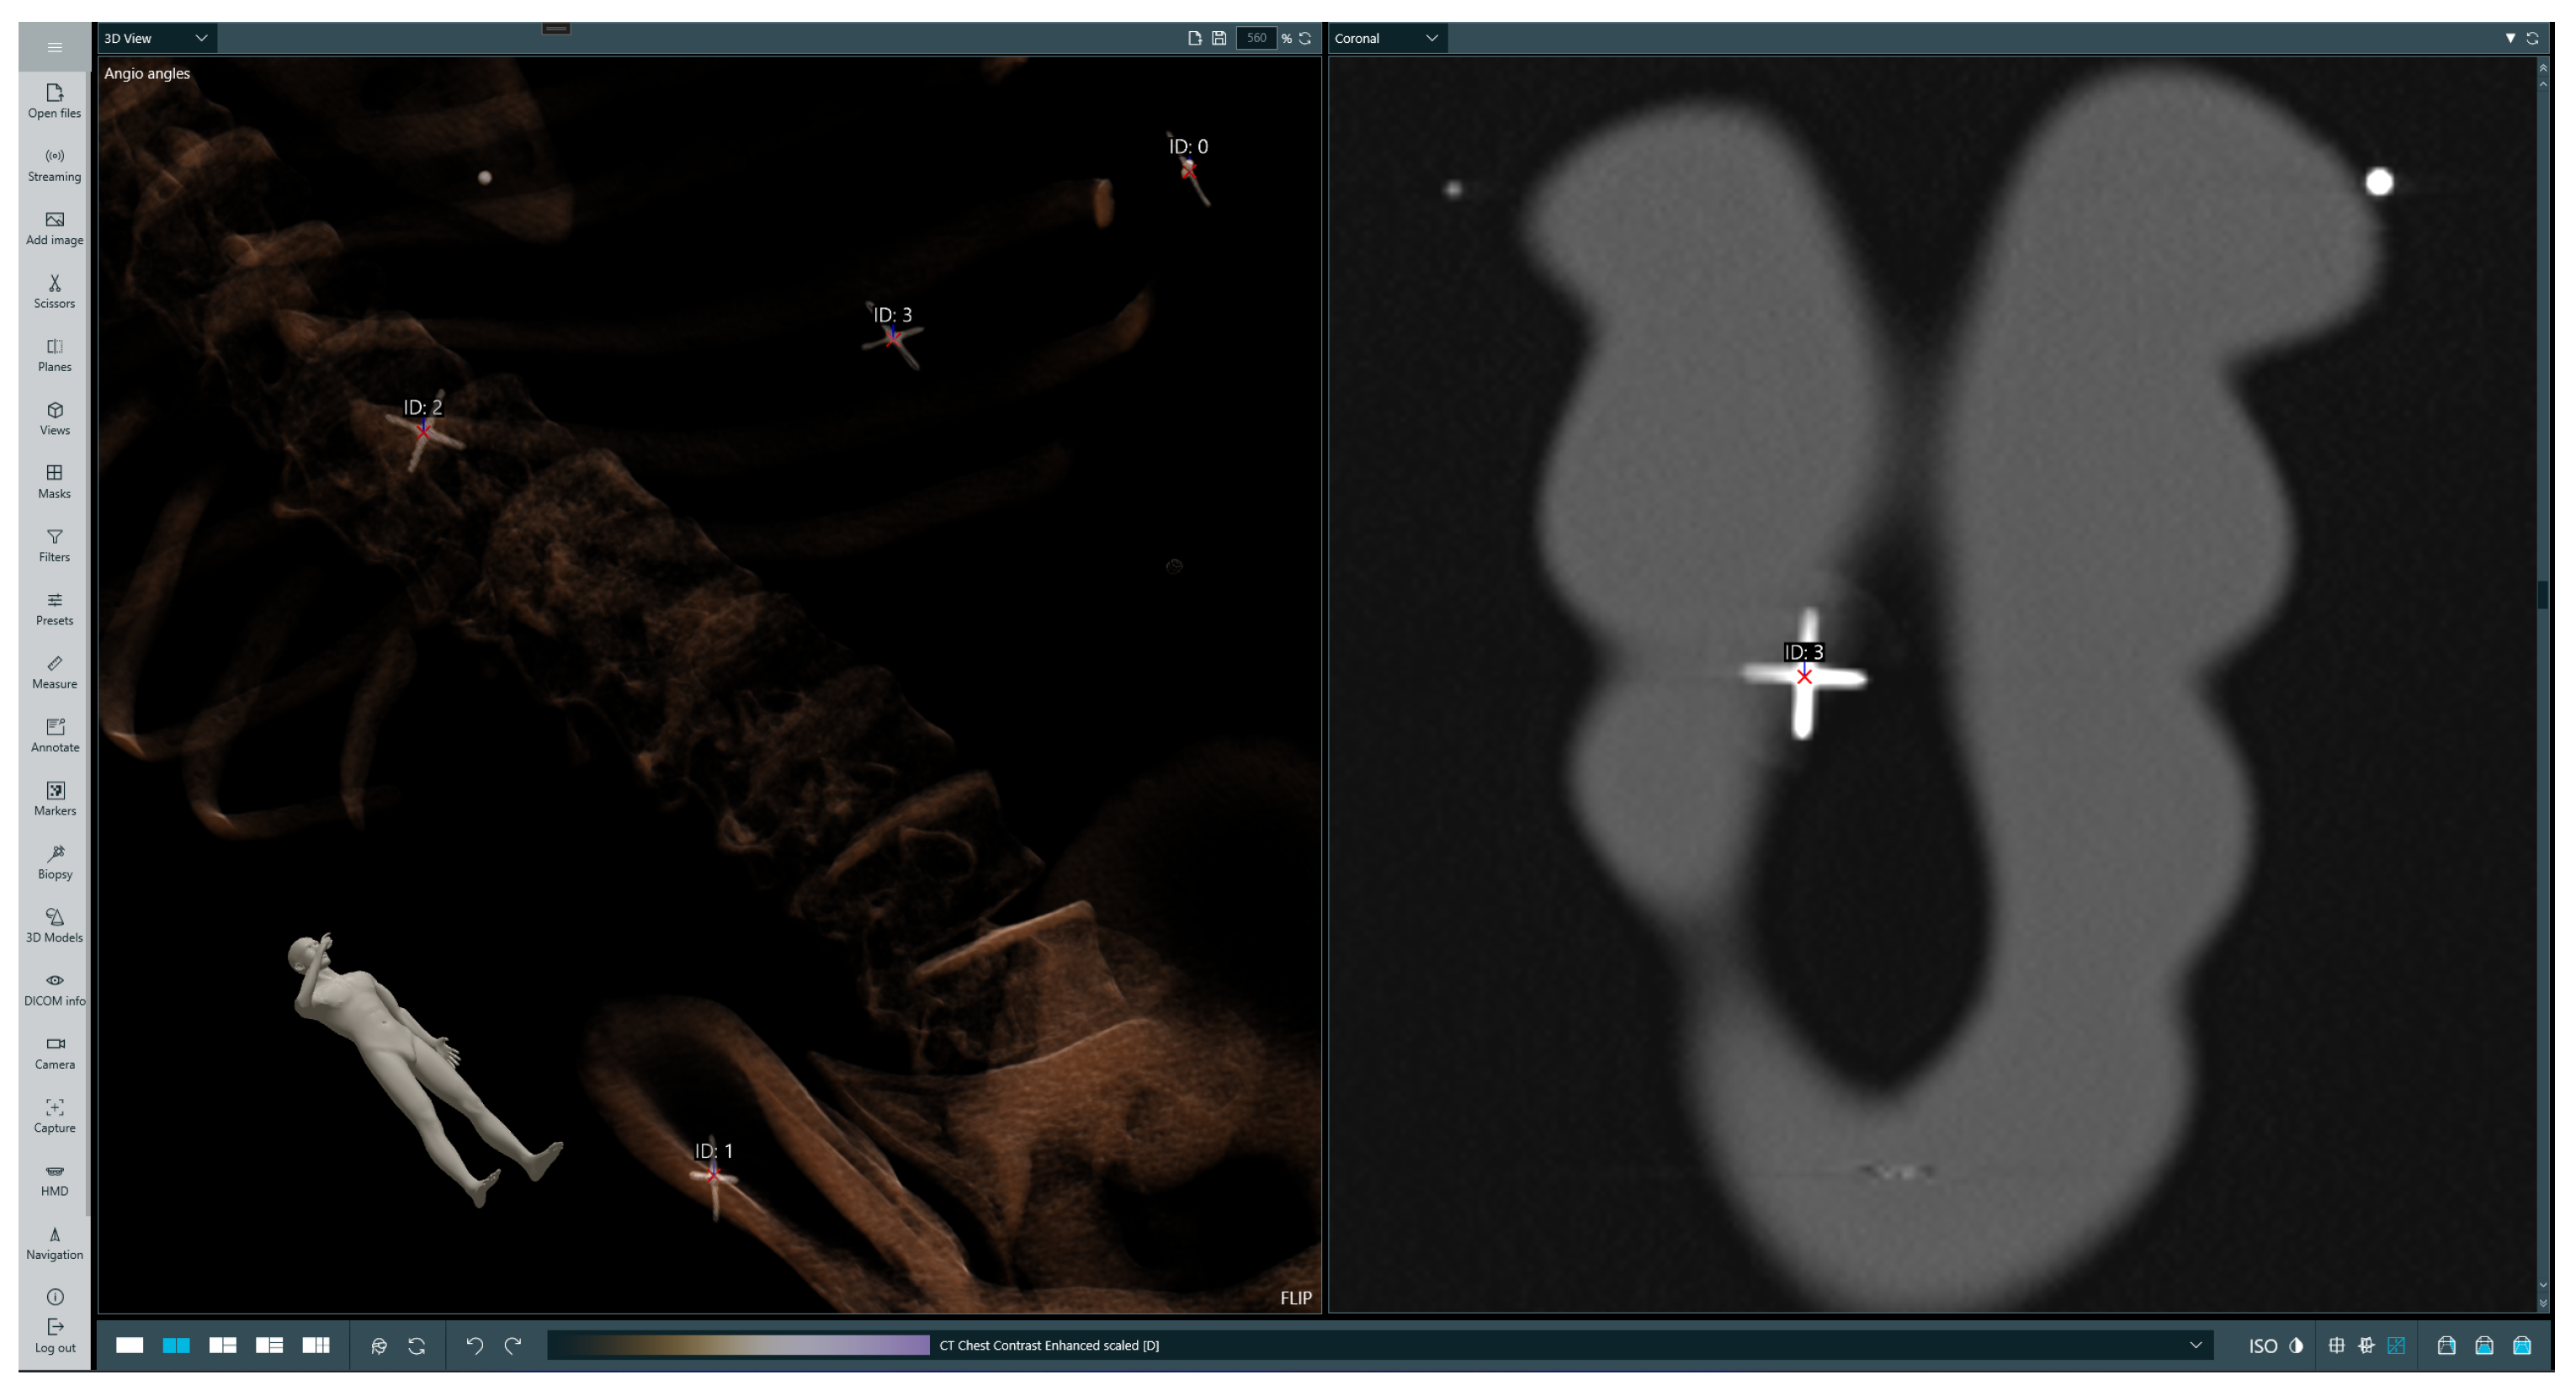

The initial step of biopsy procedure planning is selecting a trajectory along which the injection will be performed. The operator first selects a point at the target location, then a point on a skin at the injection site; afterwards, a straight line is drawn from the target spot through the injection site and above the patient’s body. There are several rings around the designated line, which are intended to guide the operator by appropriately highlighting the needle’s position in relation to the trajectory. After the trajectory is set, it can be revised by the operator in both the 3D and 2D views. This is a crucial point, at which the operator verifies the trajectory and ensures that the incision will not endanger any important organs. A sample selected trajectory is presented on Figure 4.

Figure 4.

Selected trajectory visualization. The left-hand image presents a volumetric rendering of the phantom’s CT scan with the chosen trajectory, while the right-hand image presents a 2D slice in the sagittal plane with the indicated injection site and target location. On the trajectory (red line) the first red cross symbol indicated injection point, the second landing point.

The subsequent phase involves superimposing data within the holographic space directly onto the patient’s body. To perform this process, the patient undergoes scanning with radiological markers strategically placed in specific locations of the body surface that serve as reference points and are clearly visible in the image data across multiple slices. The operator begins by selecting each marker on 2D slices, assigning them unique identifiers, and then selecting corresponding physical markers in the holographic space. Sample selected markers are presented in Figure 5. Afterwards, the hologram representing the patient’s anatomy is transformed to minimize the distance between corresponding physical and virtual markers while preserving the real scale of the patient scan. The result of superimposing the data captured by the HMD lens is presented in Figure 6.

Figure 5.

Selected markers in the data. The left-hand image presents a volumetric rendering of the phantom’s CT scan, while the right-hand image presents the 2D slice in the coronal plane with radiological marker.